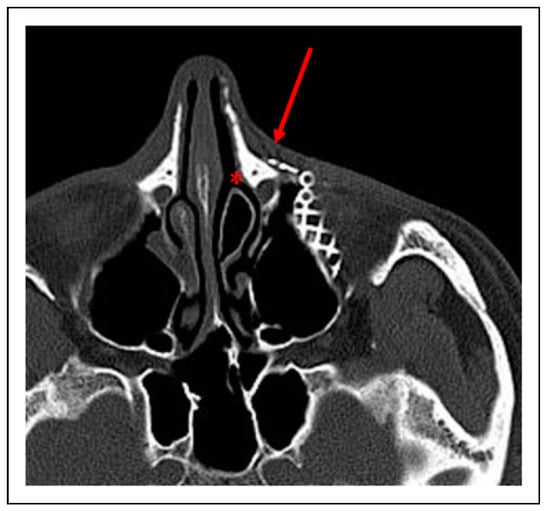

Case 1

Case 2